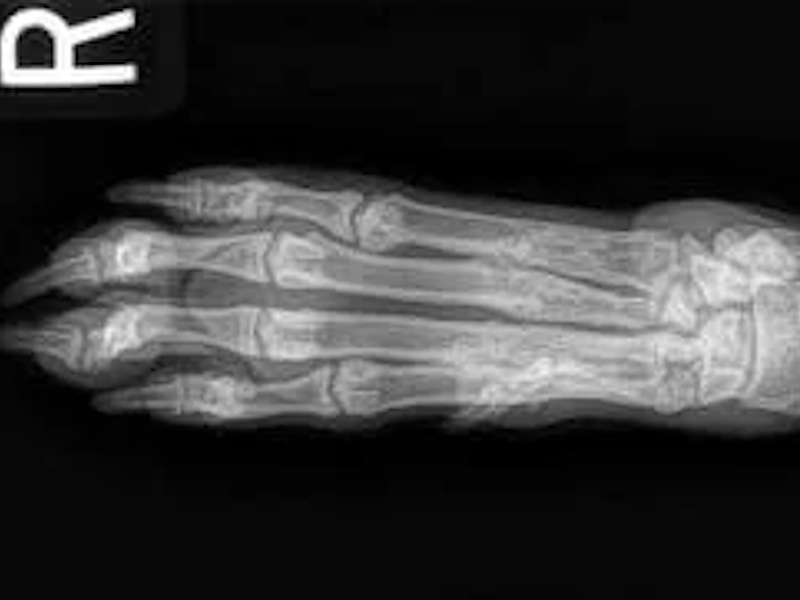

Hind Limb (Pelvis, Femur, Patella, Tibia/Fibula, Lateral Malleolus)